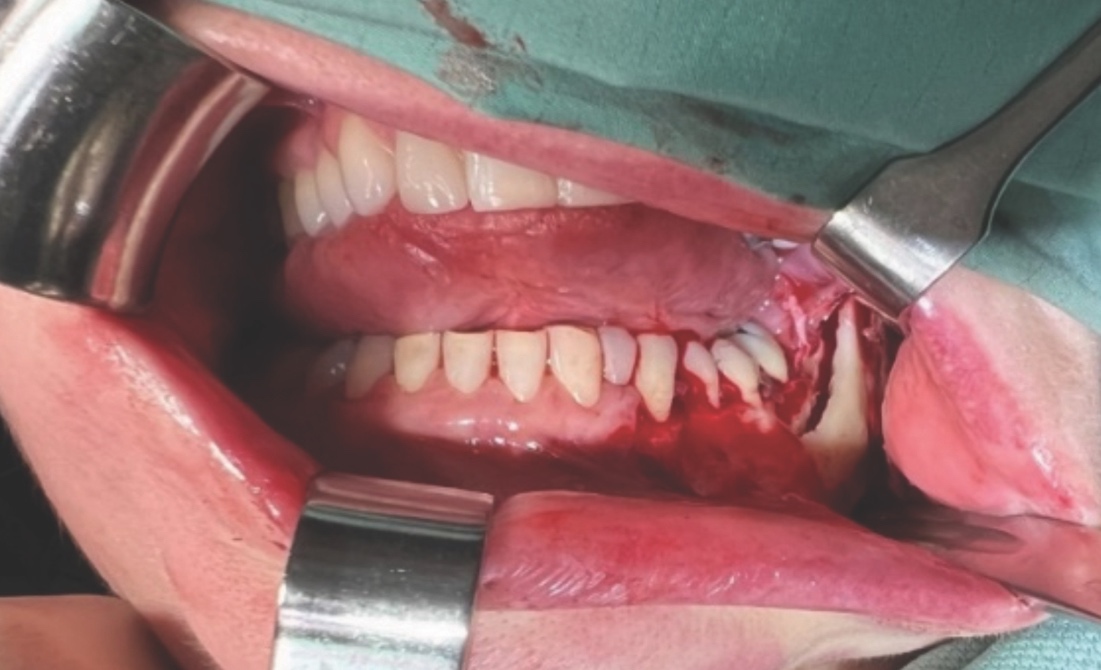

A unilateral sagittal split osteotomy was performed using piezosurgery to protect the nerve. The alveolar nerve, extending from the apical region of the left first and second molars to the mental foramen, was uncovered, and a meticulous dissection was performed to release it from the canal. Notably, rigid paste debris was observed in proximity to and within the nerve canal. The nerve exhibited signs of swelling and was surrounded by granulation tissue (Figures 4 and 5).